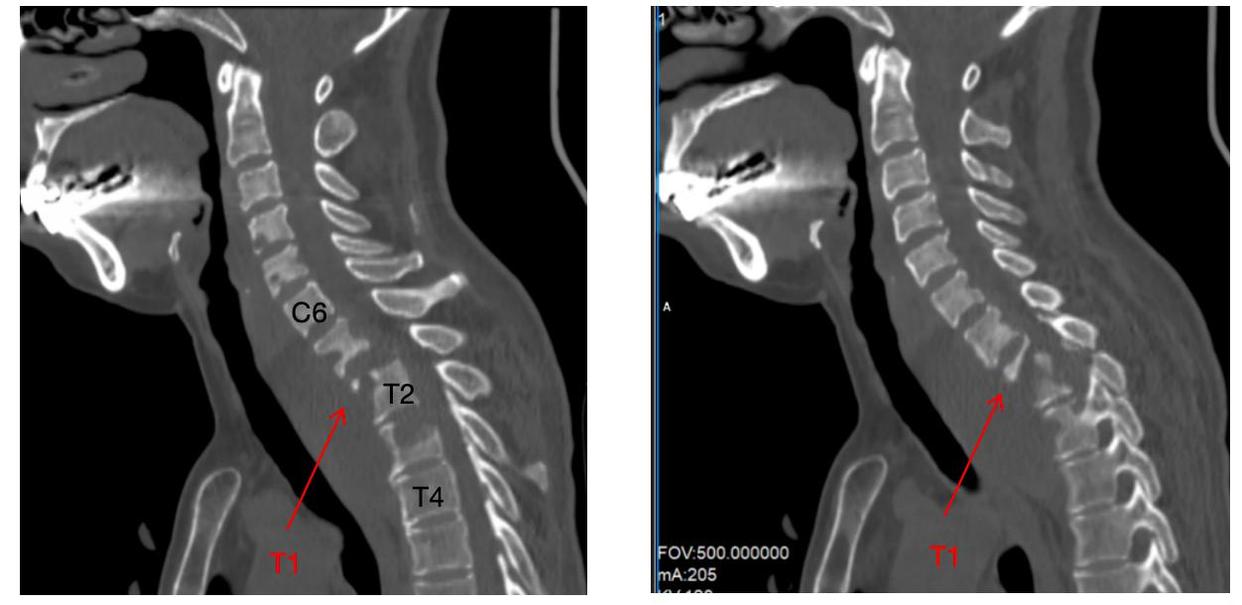

危急时刻,在朋友的建议下,艾女士辗转来到长沙市第一医院脊柱外科。入院检查结果令人揪心:8个椎体不同程度被掏空,最严重的胸1椎体被细菌啃掉90%、颈部巨大脓肿并流到椎管内压迫脊髓导致双下肢瘫痪,肩部也有巨大的脓包、重度贫血、严重营养不良。若艾女士的病情无法及时控制,必将危及生命。

为挽救患者神经功能,抢救患者生命,向伟能迅速组织多学科会诊,为患者量身定制个性化治疗方案:标准四联抗结核治疗、急诊一期颈椎前后路联合病灶清除植骨内固定手术。经过紧急而周密的准备,向伟能团队为艾女士实施了颈椎后路病灶清除椎管减压融合内固定术和颈椎前路病灶清除植骨融合术。历时6小时,手术团队成功将“蛀骨”病灶一网打尽,并用自体骨填补骨缺损,筑牢脊柱“支撑系统”。得益于成熟的MDT围手术期管理模式,该患者在6小时内顺利完成涵盖9个椎体的融合手术,以及后路联合前路的颈椎病灶清除术,术后患者情况稳定,直接被送返至普通病房,无需转入ICU监护。